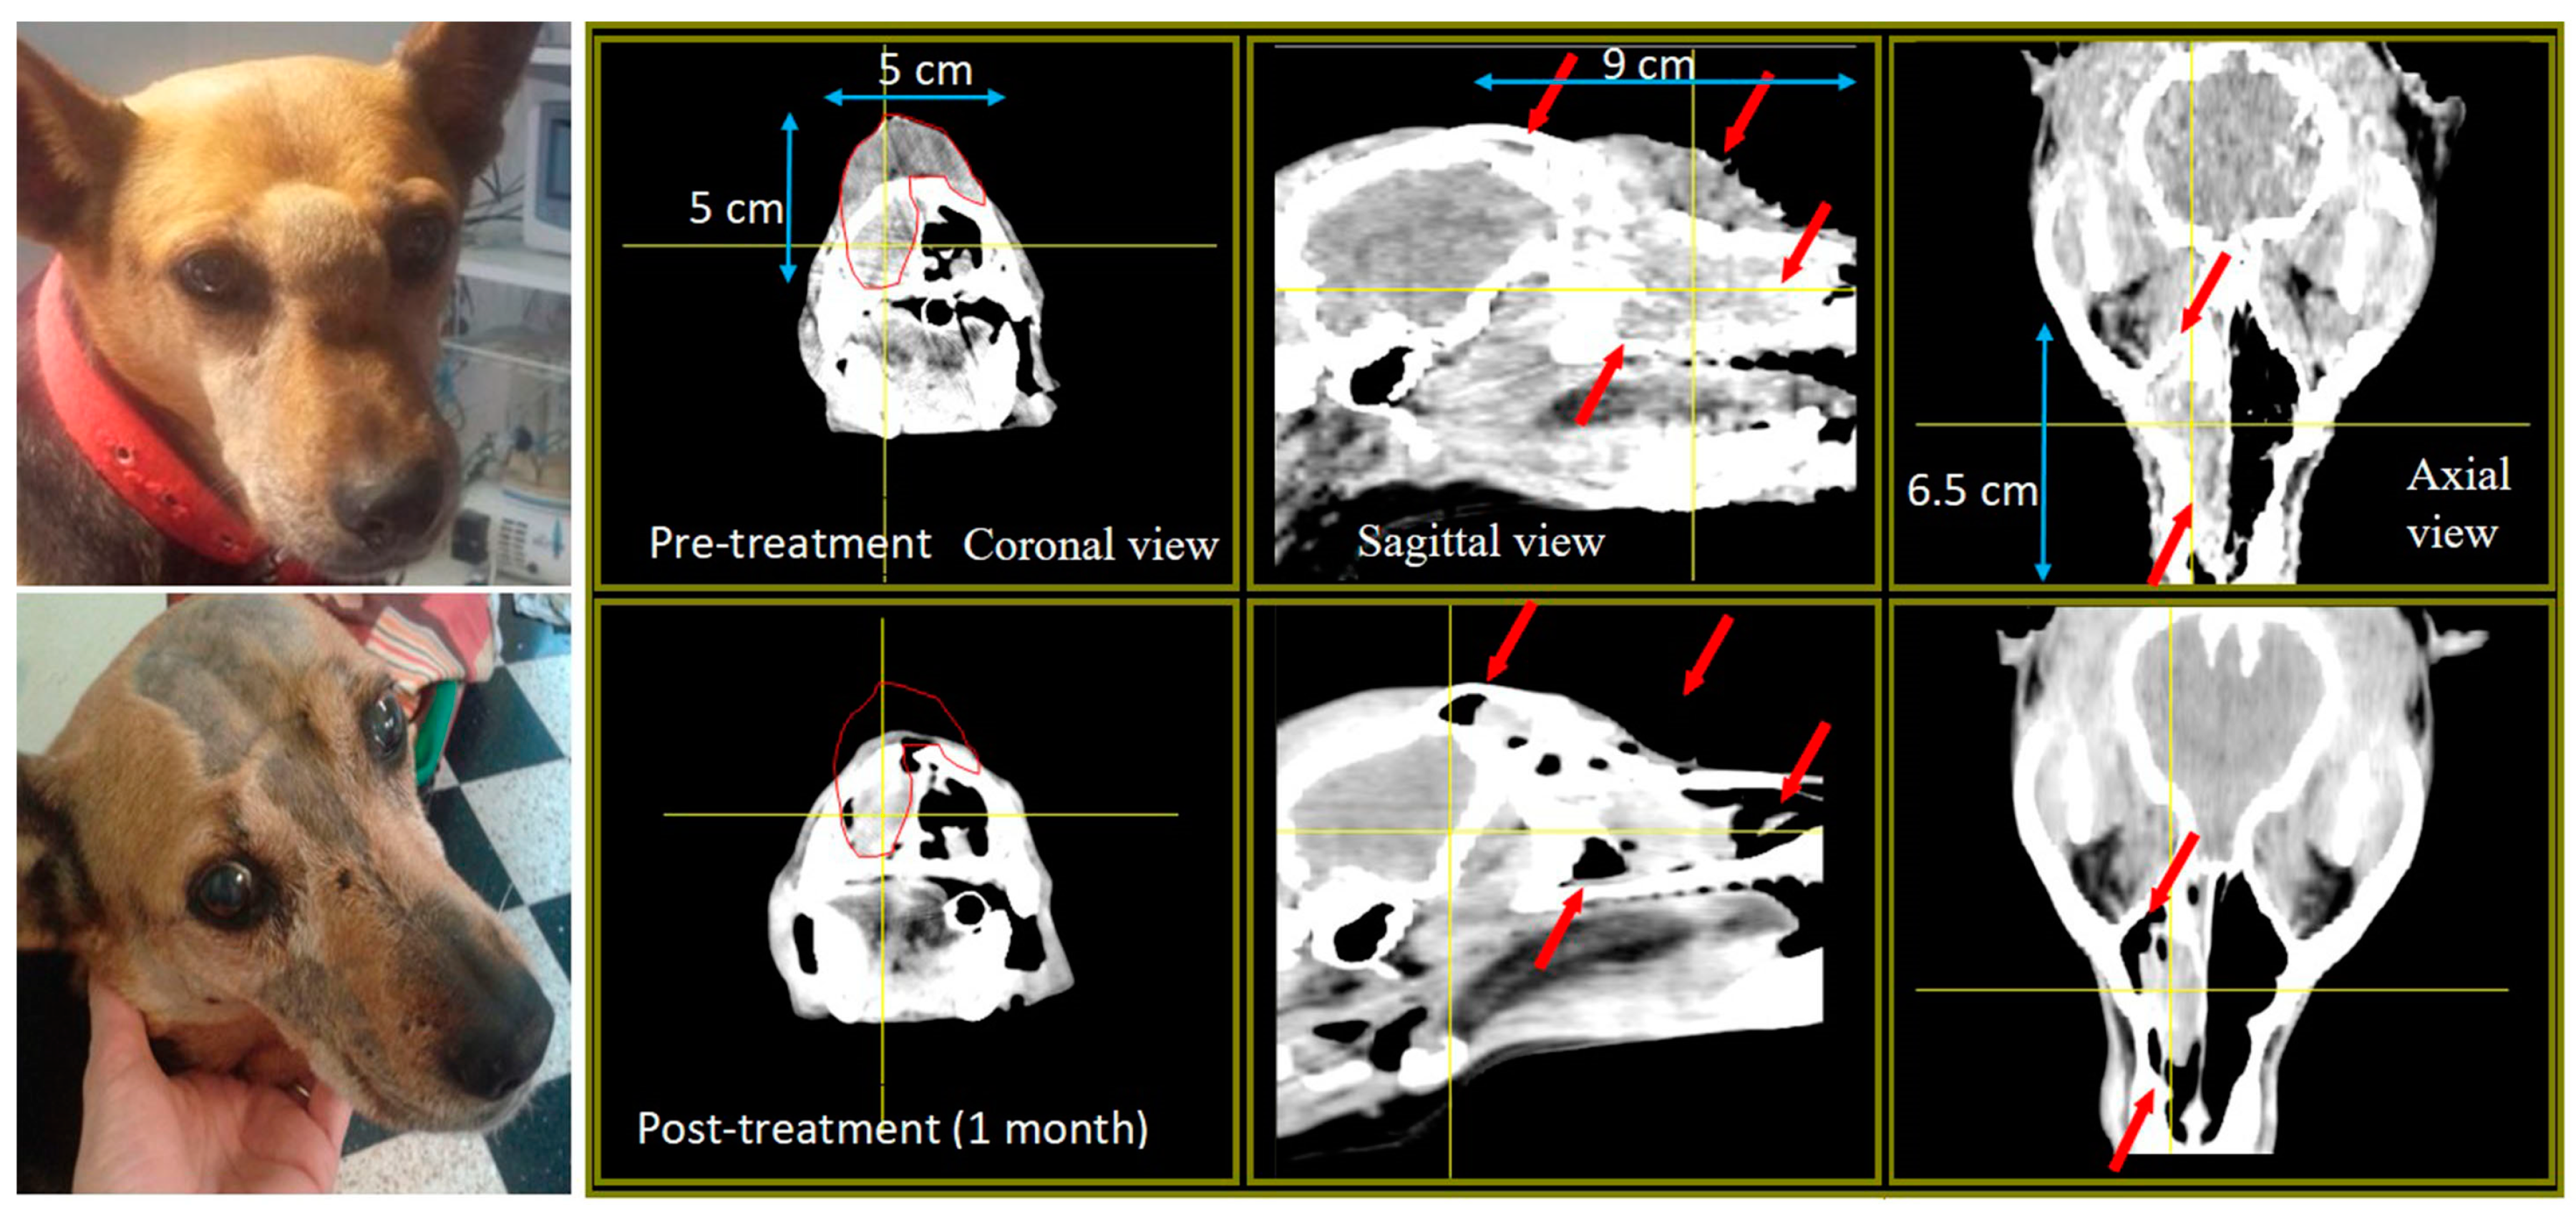

| Labrador Mora II 11 years old | Oral amelanotic melanoma TV: 12 cm3 | Surgery pre-BNCT Immuno-therapy 10 weeks post BNCT when liver and lung metastases were diagnosed | 2 appl., 4.5 weeks apart; 2 portals per appl. | PR TV 1 month post 1st appl.: 2.9 cm3 TV 2 months post 1st appl.: 0.60 cm3 Cause of death: recurrence and lung metastasis Survival post BNCT: 1 year | Mild mucositis | Positive but short-term tumor response and clinical benefit |